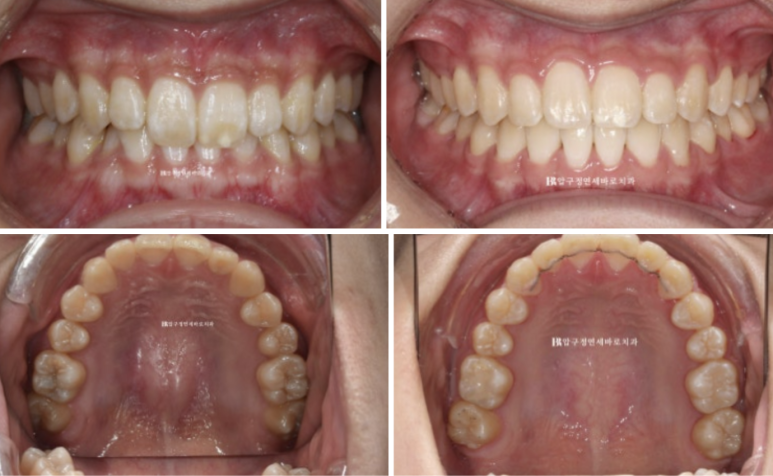

옥니를 고치고 싶어서 오신 분 입니다.

22.10

앞니가 깊게 물리는 과개교합이 보입니다.

옥니와 입매 외에도 다른 문제점이 있습니다.

앞니노출도가 적은 경우입니다,

앞니노출도가 적다는 것은 웃을때 아랫니가 많이 보이는 것 입니다.

클리피씨로 교정하기를 원하셨고 치료 목표는 옥니와 과개교합의 개선 앞니 높낮이 조절로

앞니 노출도 개선.

편평한 입매 개선으로 입술 볼륨감을 회복합니다.

여기서 환자분의 요구 한가지는 한쪽 송곳니가 더 내려와 보이니 수평을 맞춰주세요 까지입니다.